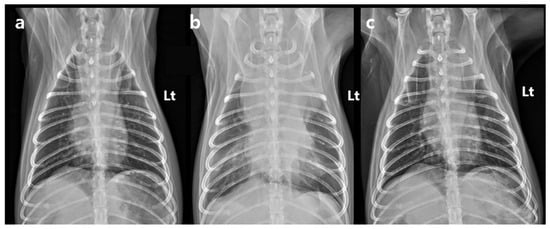

Figure 4. Serial ventrodorsal thoracic radiographs. (a) Thoracic radiograph obtained during radiation treatment planning, showing a mediastinal width of 44.7 mm. (b) Thoracic radiograph obtained 1 day after the final SBRT fraction (5 days after the first fraction of SBRT), demonstrating a marked increase in mediastinal width to 74.5 mm, increased soft tissue opacity within the mediastinum, and concurrent pleural effusion. (c) Thoracic radiograph obtained 92 days after the first fraction of SBRT, showing complete resolution of the pleural effusion and a reduction in mediastinal width to 43.4 mm. SBRT, stereotactic body radiotherapy. Lt: left.

The dog remained clinically stable throughout the SBRT course. The dog completed all three planned SBRT fractions without treatment interruption and remained clinically stable under anesthesia during all sessions. However, the day after the final fraction (5 days after the first fraction), the dog developed acute dyspnea, characterized by increased inspiratory effort and mild open-mouth breathing. Clinical signs of anemia were also evident, as the mucous membranes appeared markedly pale, capillary refill time was prolonged to approximately 2.5 s, and the patient exhibited lethargy with reduced responsiveness to external stimuli. Hematologic testing revealed decreased platelet count (124 × 103/μL), red blood cell count (4.04 × 106/μL), hemoglobin (9.0 g/dL), and hematocrit (28.8%). To rule out an underlying coagulopathy, coagulation testing was performed, and the results showed that PT (10.4 s; reference range: 5–15 s), aPTT (29.2 s; reference range: 15–45 s), and fibrinogen concentration (2.7 g/L; reference range: 1–3 g/L) all remained within normal limits. Thoracic radiographs showed increased cranial mediastinal width (74.5 mm), swelling in submandibular and axillary regions, and pleural effusion (Figure 4). On palpation, the swelling in the bilateral submandibular and axillary regions was cool to the touch, soft, and pitting, with well-defined margins. There was no local warmth, erythema, or pain on palpation. The swelling was symmetrical and corresponded anatomically to the drainage area of the cranial vena cava, suggesting congestion secondary to venous compression rather than inflammatory or neoplastic infiltration. Thoracic ultrasonography revealed a heterogeneous, hypoechoic mass adjacent to the mediastinal lesion, with no detectable vascular flow signals on color Doppler imaging. Transthoracic echocardiography demonstrated a decreased left ventricular internal dimension during both diastole and systole, with preserved global systolic and diastolic function, and no evidence of structural cardiac abnormalities. Anechoic fluid accumulation was observed between the lung parenchyma and thoracic wall, consistent with pleural effusion (Figure 5). Based on the imaging and hematological findings, cranial vena cava compression secondary to tumor-related hemorrhage and hematoma formation associated with the irradiated mass was considered the most likely diagnosis. Other possible differential diagnoses included a necrotic portion of the tumor, abscess formation with inflammation, or a metastatic lesion.

On day 2 post-SBRT (6 days after the first fraction of SBRT), anemia worsened with further decreases in the red blood cell count, hemoglobin concentration, and hematocrit to 3.46 × 106/μL, 7.7 g/dL, and 24.8%, respectively. Thoracic radiography revealed a slight decrease in cranial mediastinal width (to 70.5 mm). Following conservative management with intravenous fluid therapy and supportive care, the blood results began to progressively improve. On day 3 post-SBRT (7 days after the first fraction of SBRT), red blood cell count increased to 3.78 × 106/μL, hemoglobin concentration to 8.5 g/dL, and hematocrit to 26.4%. Thoracic radiography revealed a further small decrease in cranial mediastinal width (to 68.5 mm). By day 4 post-SBRT (8 days after the first fraction of SBRT), the red blood cell count, hemoglobin concentration, and hematocrit increased again to 4.00 × 106/μL, 9.1 g/dL, and 28.0%, respectively. Mediastinal width decreased again to 63.7 mm, and soft tissue swelling in the submandibular and axillary regions was resolved, at which point the dog was discharged. Follow-up evaluations performed after discharge (on days 5, 7, and 12 post-SBRT) revealed that the patient remained clinically stable without recurrence of dyspnea. Hematologic parameters continued to improve, with red blood cell count, hemoglobin concentration, and hematocrit increasing to 4.38 × 106/μL, 10.1 g/dL, and 30.7% on day 5 post-SBRT (9 days after the first fraction of SBRT); 5.29 × 106/μL, 12.2 g/dL, and 38.3% on day 7 post-SBRT (11 days after the first fraction of SBRT); and 5.35 × 106/μL, 12.5 g/dL, and 39.5% on day 12 post-SBRT (16 days after the first fraction of SBRT), respectively. Importantly, reticulocyte counts and percentages, which had remained within reference intervals (count: 8.4–129.3 × 109/L; percentage: 0.1–2.0%) through day 4 post-SBRT, showed a marked increase during subsequent follow-up. On day 5 post-SBRT, reticulocyte values rose to 178.4 × 109/L (4.07%), exceeding the upper reference limit. This regenerative response became more pronounced on day 7 post-SBRT, when reticulocytes peaked at 391.3 × 109/L (7.4%). By day 12 post-SBRT, reticulocyte numbers remained elevated at 365.6 × 109/L (6.84%). This temporal pattern—initially normal reticulocyte levels followed by a delayed and robust increase—provides clear evidence of a regenerative response, consistent with recovery from acute hemorrhagic anemia. The sequential changes in hematologic parameters are summarized according to the clinical timeline (Figure 6). Serial hematologic data are detailed in Supplementary Table S2.

At follow-up, the dog remained in a stable condition, with normal respiratory function and no recurrence of swelling in the submandibular or axillary region. Follow-up CT was performed on day 33 post-SBRT (37 days after the first fraction of SBRT), not primarily to assess tumor shrinkage but rather to evaluate potential treatment-related complications. Specifically, the scan was intended to monitor for tumor-associated hemorrhage and hematoma formation, to assess compression of adjacent vascular and mediastinal structures, and to rule out bleeding from surrounding normal organs. The CT showed an overall increase in tumor dimensions (length: 42.1 mm; width: 49.0 mm; height: 40.0 mm). Tumor volume increased from 25.0 cm3 to 46.4 cm3; however, the contrast-enhancing portion decreased by approximately 25% to 18.7 cm3. This decrease was accompanied by a relative increase in the non-enhancing component of the mass (pre-contrast: 30 HU; post-contrast: 31.5 HU), which exerted compression on the cranial vena cava (Figure 1c,d). Based on imaging features, hematologic findings, and the clinical course, the non-enhancing region was interpreted as a tumor-related hemorrhage secondary to radiation therapy. Thoracic radiography performed on day 88 post-SBRT (92 days after the first fraction of SBRT) revealed a further reduction in the mediastinal width to 43.4 mm, with no evidence of pleural effusion (Figure 4). The dog remained clinically stable, without any evidence of dyspnea, lethargy, or other signs of anemia. At the last follow-up on day 143 after the first SBRT fraction (139 days after completion of the final fraction), the patient was still clinically stable without recurrence of dyspnea or anemia-related signs. Thoracic radiographs at that time showed no significant changes compared with those obtained on day 88 post-SBRT (Figure 4c).